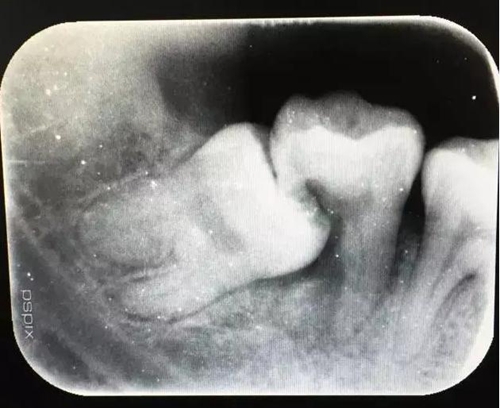

圖2.術(shù)前的x線根尖片影像檢查:47遠(yuǎn)中牙根吸收。

11.jpg